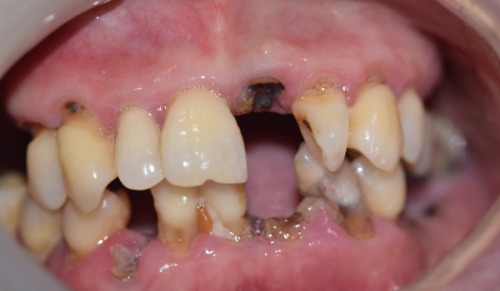

任何修复体都可能出现问题,烤瓷牙也不例外。比较常见的问题包括:牙龈边缘发黑、瓷层崩裂、牙齿敏感、继发龋齿等。

牙龈边缘发黑很多时候是由于金属的渗透导致的,特别是在使用非贵金属材料时更容易出现。瓷层崩裂可能与咬合力过大或者制作工艺有关。牙齿敏感则可能是因为备牙过程中对牙体组织刺激较大,或者粘接环节处理得不够完善。